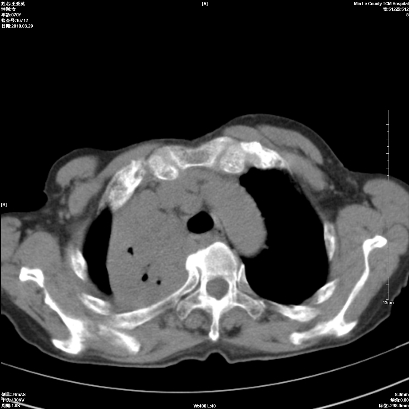

标题: CT25424:女性,70岁,胸闷、咳嗽月余。 [打印本页]

右肺上叶支气管开口阻塞,上叶呈不均匀致密影,右肺中下叶内见斑片状密度增高影,上叶见钙化点,纵隔内见钙化淋巴结,桶状胸,右下肺动脉增粗,残根征,意见:1.右肺中心性肺癌;2.右肺陈旧性结核;3.肺心病。

1)考虑右肺中央型肺癌伴右肺上叶肺不张,右肺门淋巴结转移;建议行支纤维镜检查。2)右肺中叶、下叶及左肺上叶舌段感染性病变。3)肝内多发低密度影,不排除转移瘤可能;建议行ct增强扫描检查。

ct所见:右肺上叶肺不张,呈软组织密度影向肺门区聚拢,其内可见含气段支气管及细支气管影,病灶内尚可见钙化结节。右肺上叶支气管狭窄,段支气管壁可见钙化。右肺下叶背段、右肺中叶见不规则小片絮状影及纤维条索影,形态较僵硬。右肺中叶胸膜旁可见多个小结节影。纵膈内见钙化淋巴结。

分析:右侧胸廓及右肺体积缩小,说明病变时间比较长了,应该是有数年的时间了,如果是短期内出现的肺不张,只会引起纵膈向患侧移位,而不会引起胸廓的塌陷。不张的肺组织内可见含气支气管影,说明右肺上叶支气管没有完全中断,只是狭窄。右肺中叶、下叶散在不规则病灶,部分呈纤维化改变。纵膈内的淋巴结大部分钙化。因此,本例给我的感觉良性病变的可能是大。

结论:考虑右肺上叶支气管内膜结核合并右肺上叶肺不张;右肺中叶、下叶陈旧性肺结核改变。